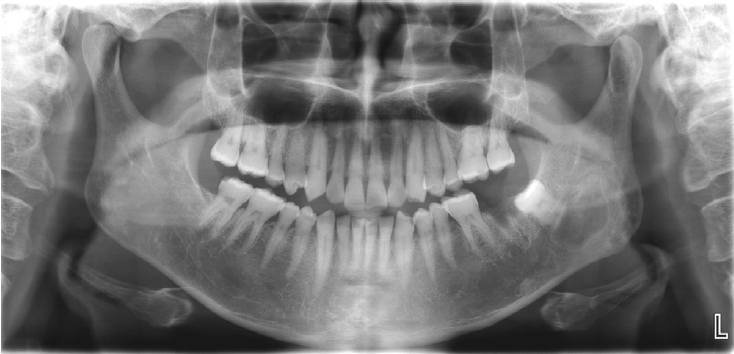

Fig. 2.

Axial, parapanoramic, and cross-sectional cone-beam computed tomographic images show a radiolucent lesion with a well-corticated margin and subtle internal calcified foci. Generalized sclerotic changes in the adjacent cancellous bone and thinning of the buccolingual cortex are noted, with mild expansion of the lingual cortex due to the lesion.

A 52-year-old male was referred to the Gangneung-Wonju National University Dental Hospital, from a local dental clinic for evaluation of a lesion in the left mandibular angle and ramus. The lesion had been identified on a panoramic image obtained for the extraction of the left mandibular second molar, five days prior to presenting to our hospital. Clinical examination, including both intraoral and extraoral assessments, revealed no remarkable findings.The patient underwent a panoramic radiograph and cone-beam computed tomography (CBCT). The panoramic radiograph showed an ovoid, well-demarcated radiolucency with irregular contour, and internal lytic change beneath the periapical area of the left mandibular third molar region (Fig. 1). CBCT demonstrated a radiolucent lesion with a well-corticated margin and subtle internal calcified foci. Generalized sclerotic changes in the adjacent cancellous bone and thinning of the bucco-lingual cortex were noted, with mild expansion of the lingual cortex due to the lesion (Fig. 2). Anatomically, the lesion lay inferior to the mandibular canal and outside the tooth-bearing alveolus, which argued against an odontogenic origin. Collectively, these features were interpreted as a radiolucent lesion with surrounding sclerosis. Routine laboratory tests (L30 clinical chemistry panel) revealed elevated glucose (135 mg/dL) and total cholesterol (233 mg/dL), while all other parameters were within normal limits. Based on the clinical and radiographic findings-posterior mandibular location, well-defined unilocular radiolucency with a pronounced adjacent sclerotic change, cortical thinning with mild expansion but without periosteal reaction or cortical breach, and non-odontogenic position—the working differential favored non-ossifying fibroma, with a simple bone cyst considered less likely.Histopathological analysis of the decalcified mandibular specimen revealed a mass predominantly composed of brown fat cells. Within the lesion, focal areas of cholesteatoma-like formation and numerous variably sized bony particle deposits were identified. Tumor cells exhibited eosinophilic granular cytoplasm with eccentric nuclei, consistent with adipocytic differentiation. Notably, the majority of the mass consisted of polygonal brown fat cells displaying multiple cytoplasmic vacuoles (Fig. 3). Based on the imaging appearance, the differential diagnosis favored non-ossifying fibroma, with simple bone cyst considered less likely. Intraosseous hibernoma was not initially suspected and was confirmed postoperatively by histopathologic examination. Overall, the findings supported a diagnosis of a lesion with extensive brown fat cells proliferation and secondary changes including bony particle deposition and cholesteatoma-like formation. These findings established the final diagnosis of intraosseous hibernoma. The patient has been followed periodically, and a 7-month postoperative panoramic radiograph and CBCT showed new bone formation along the superior, inferior, and lingual aspects of the postoperative defect consistent with healing, without evidence of recurrence (Fig. 4).